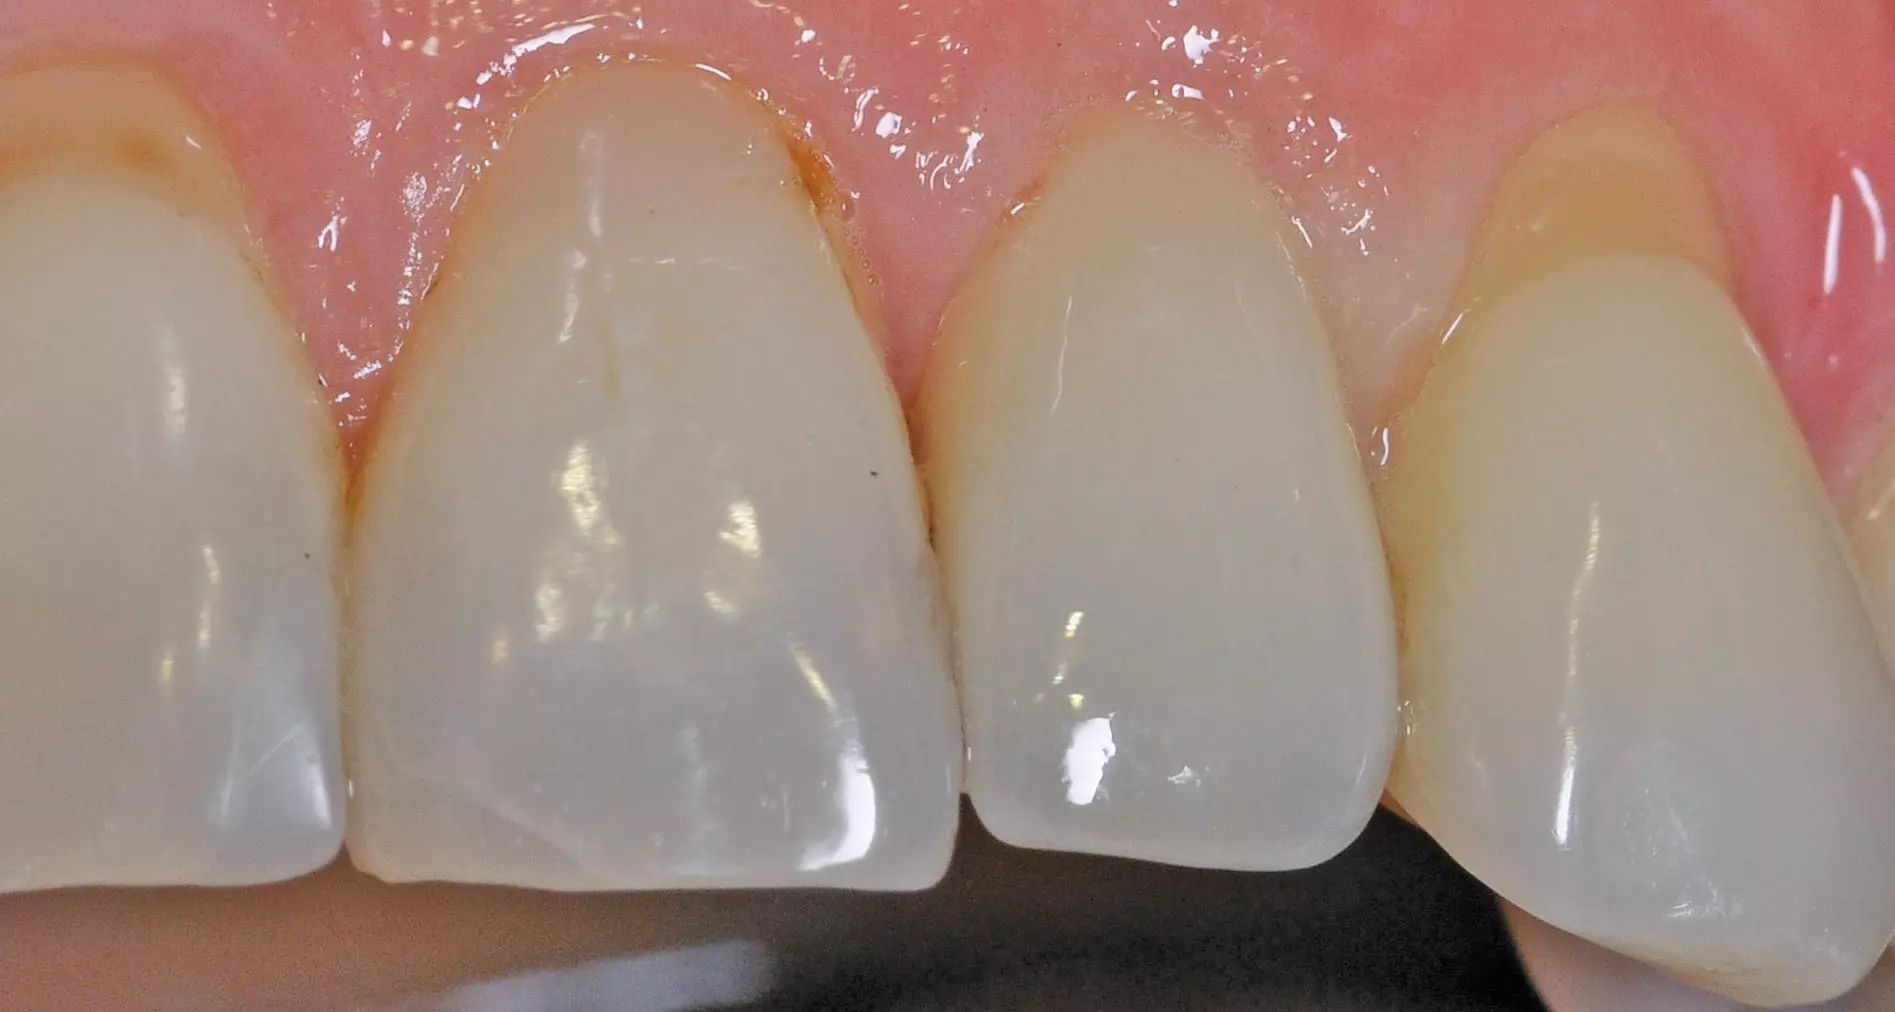

Präklinische und klinische Untersuchungen zu parodontologischen Parametern um „gesunde“ Titan- und Zirkonimplantate zeigen in Bezug auf die Sulcustiefen statistisch signifikante Unterschiede [36,37]. Die Werte erweisen sich sowohl im Tiermodell als auch beim Patienten höher bei den Titanimplantaten im Vergleich zu den Zirkonoxidimplantaten. Erfahrungsgemäß ist eine Sulcus-Sondierung am Zirkonoxidimplantat allerdings aufgrund der dichten fibrösen Gewebestruktur erschwert (Abb. 3).

Dr. Jacobi-Gresser

Augenscheinlich sind die ästhetischen Vorteile des Zirkonoxid-Implantatwerkstoffes im Vergleich zum Titan insbesondere in der anterioren ästhetischen Zone bei Patienten mit dünner Gingiva unter 2 mm [47] (Abb. 5–8).